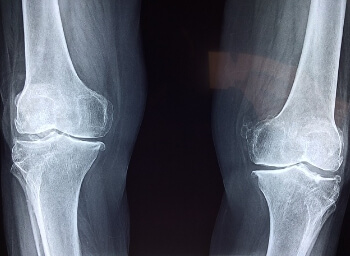

무릎에서 뚝뚝 소리가 나는 이유

1. 관절 거품

무릎의 관절에는 관절을 부드럽게 움직일 수 있는 윤활액이 포함되어 있는데요. 관절이 움직이는 동안 관절에 다양한 압력이 가해지게 되고 부위별 압력이 달라서 이러한 압력의 변화로 인해서 윤활액의 내에서 기포가 형성되기도 하고 터지면서 거품이 사라지기도 하는데, 이러한 상황 속에서 기포가 터지면서 소리가 발생할 수 있습니다.

2. 인대 힘줄의 움직임

무릎을 둘러싸고 있는 인대와 힘줄이 원래의 자리에서 벗어나기도 하고 특정한 움직임중에 갑자기 원래의 자리로 돌아오기도 하는데 이러한 움직임 속에서 소리가 나기도 합니다.

3. 반월판 파열

무릎의 관절을 완충시키는 연골인 반월판이 찢어지고 손상되는 경우 찢어진 자리의 불규칙한 움직임으로 인해서 무릎을 굽히고 펴는 동작에서 갑작스러운 소리가 발생할 수 있습니다.

4. 관절 표면의 불규칙함

무릎내의 거친 연골이나 작은 뼈들의 불규칙한 표면이 활동을 하는 동안 마찰을 하면서 소리를 일으킬 수 있습니다.

5. 염증과 관절염

무릎 관절의 염증이 인대와 힘줄등의 변화을 일으켜서 서로 마찰하면서 움직일 때 서로 마찰하면서 소리를 낼 수도 있고, 관절염이 있는 경우에 관절의 표면이 불규칙해져서 움직일 때 뚝뚝 거리는 등 소리가 발생하기도 합니다.

보통 나이가 들면서 관절의 표면이 마모되고 찢어지면서 불규칙해지고 조직의 탄력성도 감소합니다. 일반적으로 무릎의 부기가 없이 가끔씩 소리가 나는 것은 사실 정상적인 수준이라고 여겨질 수 있지만, 이러한 현상이 지속되고 통증이 유발되는 경우에는 전문의를 통해서 진단을 받는 것이 좋습니다.